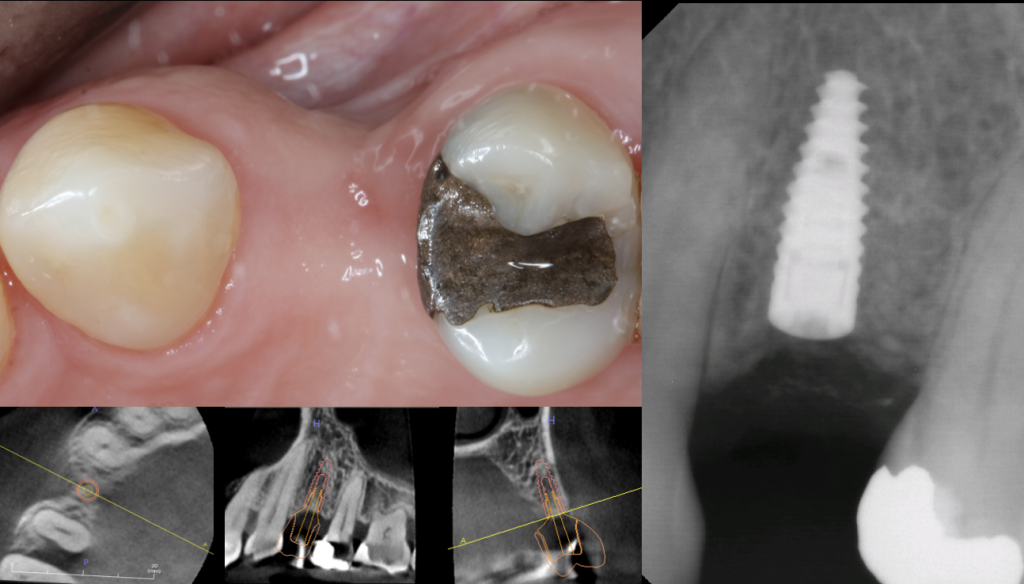

Dental implants have become the most desirable option to replace missing teeth due to their ability to integrate with our bodies and perform as natural teeth. The therapy requires careful study of the existing jawbone, and often times bone grafts are necessary to increase the bone volume to facilitate implant placement.